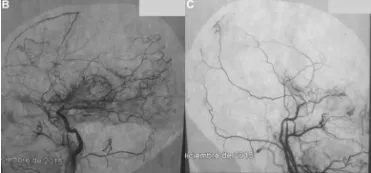

在神经外科领域,某些脑血管的形态悄然诉说着一种隐匿的危机。它不是肿瘤的占位效应,也非典型的动脉瘤膨出,而是一种以颅内颈内动脉末端为中心,渐进性的狭窄乃至闭塞,伴随其侧支循...

提到脑卒中,很多人会想到高血压、动脉硬化,却不知一种名为烟雾病的脑血管疾病,正成为儿童和中老年人脑卒中的重要诱因。 这种病因脑血管造影时呈现出烟雾状的异常血管网而得名,看...

烟雾病是一种特殊的脑血管疾病双侧颈内动脉慢慢变窄,大脑底部长出密密麻麻的烟雾状代偿血管网。 对于成年患者,直接搭桥手术是目前最有效的治疗方式之一:把头皮上的颞浅动脉接到大...